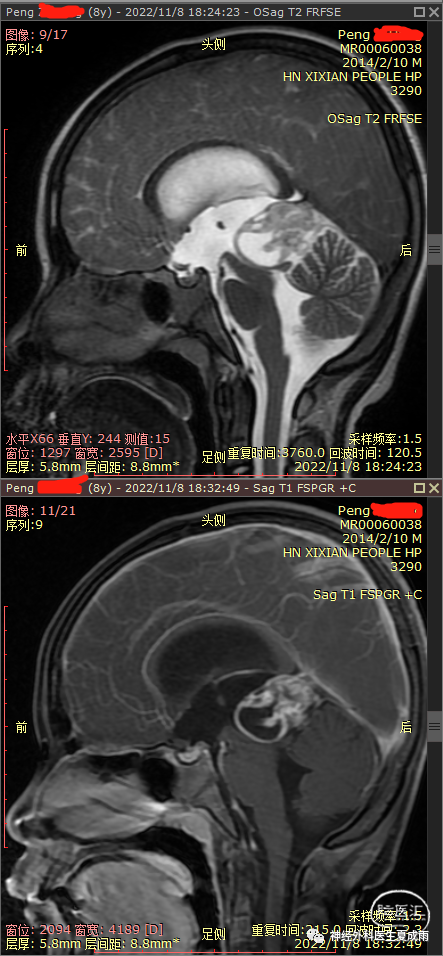

外院磁共振⏬

根据术前影像有钙化,强化不均匀,无尿崩,以及血清AFP增高,考虑为非生殖细胞瘤的生殖细胞肿瘤,建议首选行肿瘤切除术。